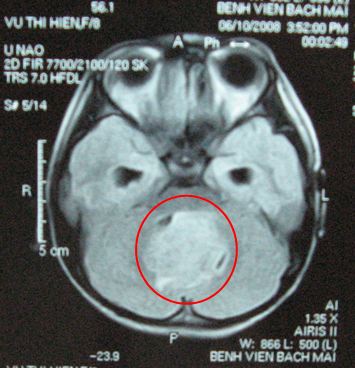

Trường hợp 2: Bệnh nhân Nguyễn Thị M. ,nữ 15 tuổi, vào viện vì lí do đau đầu, buồn nôn, nôn, thị lực 2 mắt giảm.

Trên film chụp cắt lớp vi tính sọ não và cộng hưởng từ sọ não thấy hình ảnh khối tổn thương choán chỗ vùng hố sau kích thước 3,5x3cm.

Bệnh nhi đã được chẩn đoán u não nghĩ nhiều là U nguyên bào tủy

Bệnh nhân đã được phẫu thuật lấy u tối đa, sau đó xạ trị gia tốc toàn não và tủy 36Gy, xạ trị bổ trợ thêm vào diện u để đạt liều xạ trị tại u là 56,8Gy.

Tiếp theo đó bệnh nhân được điều trị hóa chất 08 đợt

Hiện tại bệnh nhi hoàn toàn khỏe mạnh, không liệt, không đau đầu, không nôn bệnh nhi đã trở lại cuộc sống bình thường và đi học trở lại.

Trên phim chụp cộng hưởng từ toàn thân: không có tổn thương tái phát hoặc di căn.

Tổn thương u trước điều trị: khối u vùng hố sau kích thước 3,5x3cm

Sau điều trị, tổn thương u đã tan biến hoàn toàn